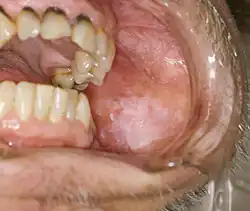

Mouth

Oral lichen planus (also termed oral mucosal lichen planus), is a form of mucosal lichen planus, where lichen planus involves the oral mucosa, the lining of the mouth.[39] This may occur in combination with other variants of lichen planus. Six clinical forms of oral lichen planus (OLP) are recognized:[40]

These types often coexist in the same individual. Oral lichen planus (OLP) tends to present bilaterally as mostly white lesions on the inner cheek,[41] although any mucosal site in the mouth may be involved. Other sites, in decreasing order of frequency, may include the tongue, lips, gingivae, floor of the mouth, and very rarely, the palate.[41]